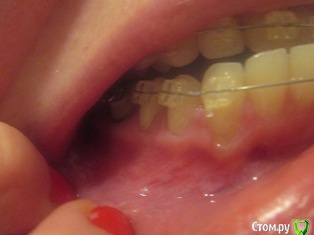

Наталья1 Опубликовано 30 марта, 2017 Автор Поделиться Опубликовано 30 марта, 2017 1) Первые 2 фото - левый нижний сегмент после операции,2) 3 следующих фото - правый нижний сегмент без операции ( требуется ли? ИМХО, разница в высоте прикрепления десны незначительная, а какие последствия на лице!), 3) последнее фото - последствия на лице ( залом на щеке). Ссылка на комментарий